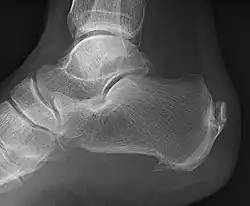

Enthesophytes are abnormal bony projections at the attachment of a tendon or ligament.[1] They are not to be confused with osteophytes, which are abnormal bony projections in joint spaces. Enthesophytes and osteophytes are bone responses for stress.[1]